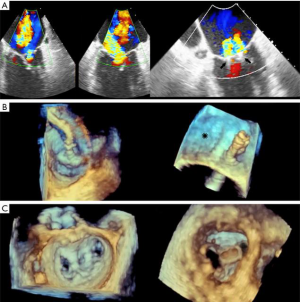

- TMVR relies on both echocardiography and CT, which are critical for patient selection, complete anatomic definition of the mitral complex, prediction of LVOT obstruction and complications diagnosis. Echocardiography is essential for procedural guidance (18,19,21,24,26,33-35). The transseptal puncture site is chosen to allow positioning of the device coaxial with the MA trajectory. A landing zone is chosen under fluoroscopic and echocardiographic guidance, monitoring for evidence of LVOT obstruction. 3D TEE is used to document full deployment of the atrial skirt and color Doppler helps detect perivalvular leaks. Sequential 2D X-plane views ascertain full leaflet capture by the device anchors, tabs or paddles, as TMVR devices do not rely on radial force for fixation. For apical delivery of TMVR devices, the location of left ventricular apical puncture is located by real time echocardiography as the operator “pokes” the ventricular apex, to identify a delivery trajectory coaxial with the MA trajectory (Figure 1) (14). TMVR procedures are divided in three categories: valve-in-valve, valve-in-ring, and valve-in-MAC (Figures 10-12, Video 4).

- CT, compared to echocardiography, lacks hemodynamic data, has lower signal to noise ratio, comparable temporal resolution and better spatial and contrast resolution, making it suitable for MV imaging (10). Operator-dependent, optimized imaging protocols for MV include: wide field of view, higher peak kV, bolus timing using time attenuation curves, left atrial contrast target, 5–10% phase intervals and specific reconstructions for annulus sizing and LVOT analysis (11). Image analysis is performed on the thinnest possible slice, using projections similar to echocardiographic views, with 4D reconstructions and multiplanar reformatting adjusted to minimize beam hardening and blooming effect. Lifelike, 4DCT cinematic rendering may be more useful compared to traditional 3D volumetric reconstructions. CT is indispensable for mitral annulus sizing and for the prediction and evaluation of LVOT obstruction risk in TMVR (Figure 3, Video 2) (10,12-22). Additionally, CT allows precise measurement of the geometric mitral valve area, predicts optimal fluoroscopic angles and identifies the location of the coronary sinus in relation with the annulus (Figure 4). Accurate sizing of the MA is critical for device choice. The least square planes method projects the 3D contour of the annulus on to a 2D plane and led to the concept of a simplified, flat, D-shaped mitral annulus, which reflects the actual planar landing zone of TMVR devices (6,23,24). A reproducible “effective annular diameter” can be derived from either the measured area, or the perimeter of the annulus (12). CT is vastly superior to echocardiography in imaging mitral annulus calcification (MAC), which can disrupt the atrioventricular groove and extend into the leaflets or the adjacent myocardium. Extensive leaflet calcification or fibrosis represents the basis of “degenerative MS” (Figure 5). MAC may involve the adjacent myocardium, or display a “caseous” core, without significant MS (Figure 6). TMVR creates a “neo-LVOT” between the basal segment of the interventricular septum and the AML, displaced anteriorly by the prosthesis struts, or flange (25). The semilunar cross-sectional area of the neo-LVOT may be measured by planimetry. Since LVOT obstruction may have profound hemodynamic consequences, several methods have been proposed to predict the risk of this complication, including proprietary software (11,24-26). Predictors of LVOT obstruction can be identified by CT, TTE or TEE: aorto-mitral angle <110°, LVOT area <2.0 cm2, length of the AML, short chordae, direct papillary muscle attachment, thickness of the basal segment of the interventricular septum and LV cavity size.